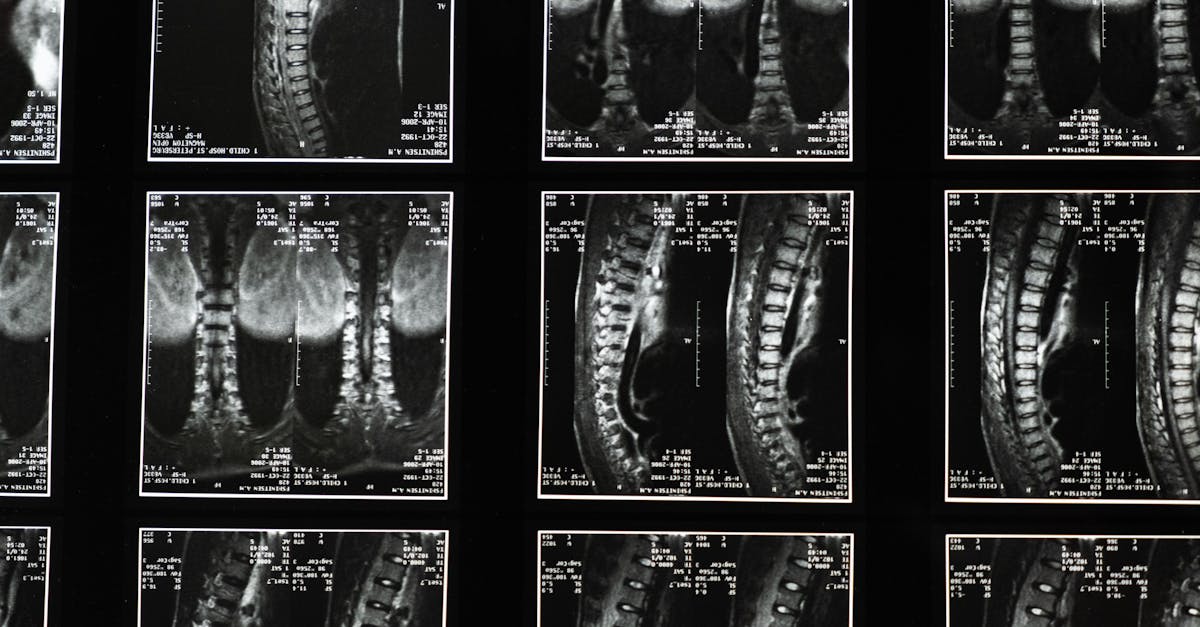

La décompression neurovertébrale est une technique qui consiste à appliquer une traction douce et contrôlée sur la colonne vertébrale. Cette méthode vise à étirer la colonne, réduisant la pression sur les disques intervertébraux et les racines nerveuses comprimées. Grâce à cet étirement, la circulation sanguine et l’oxygénation des tissus sont améliorées, favorisant ainsi le processus de guérison et d’apaisement des douleurs chroniques.

La méthode de décompression neurovertébrale agit en offrant un soulagement aux patients en relâchant la tension exercée sur les nerfs et les disques intervertébraux. Cette traction douce permet de créer un espace entre les vertèbres, ce qui aide à réduire la pression et à encourager la circulation sanguine dans les zones comprimées. Ce processus favorise non seulement la guérison, mais il contribue également à améliorer l’amplitude des mouvements et au bien-être global du patient.

Cette méthode fonctionne en appliquant une traction contrôlée. Cela permet d’augmenter l’espace entre les vertèbres, réduisant ainsi la pression sur les disques vertébraux. Une meilleure circulation sanguine dans les zones traitées favorise la guérison et aide à réduire l’inflammation, apportant un soulagement aux patients. Ce traitement s’adresse particulièrement à ceux qui rencontrent des douleurs neuropathiques dues à des problèmes comme les hernies discales.